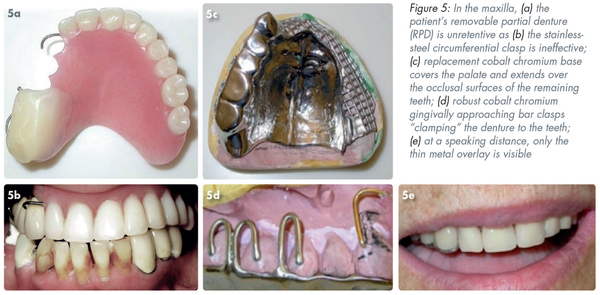

The acrylic RPD in Figure 5a is unretentive as the stainless-steel circumferential clasp on #13 is ineffective (Figure 5b) as is the use of a denture adhesive. The replacement cobalt chromium base (Figure 5c) has been designed to cover the palate and extended over the occlusal surfaces of the remaining teeth. Figure 5d shows robust cobalt chromium gingivally approaching bar clasps “clamping” the denture to the teeth #17, 16, and 15. Retention is further aided by the gold TWA on #13. In Figure 5e the only component that is visible at a speaking distance is the thin metal overlay on the canine, the reflective aspect of which has been dulled with sand blasting.